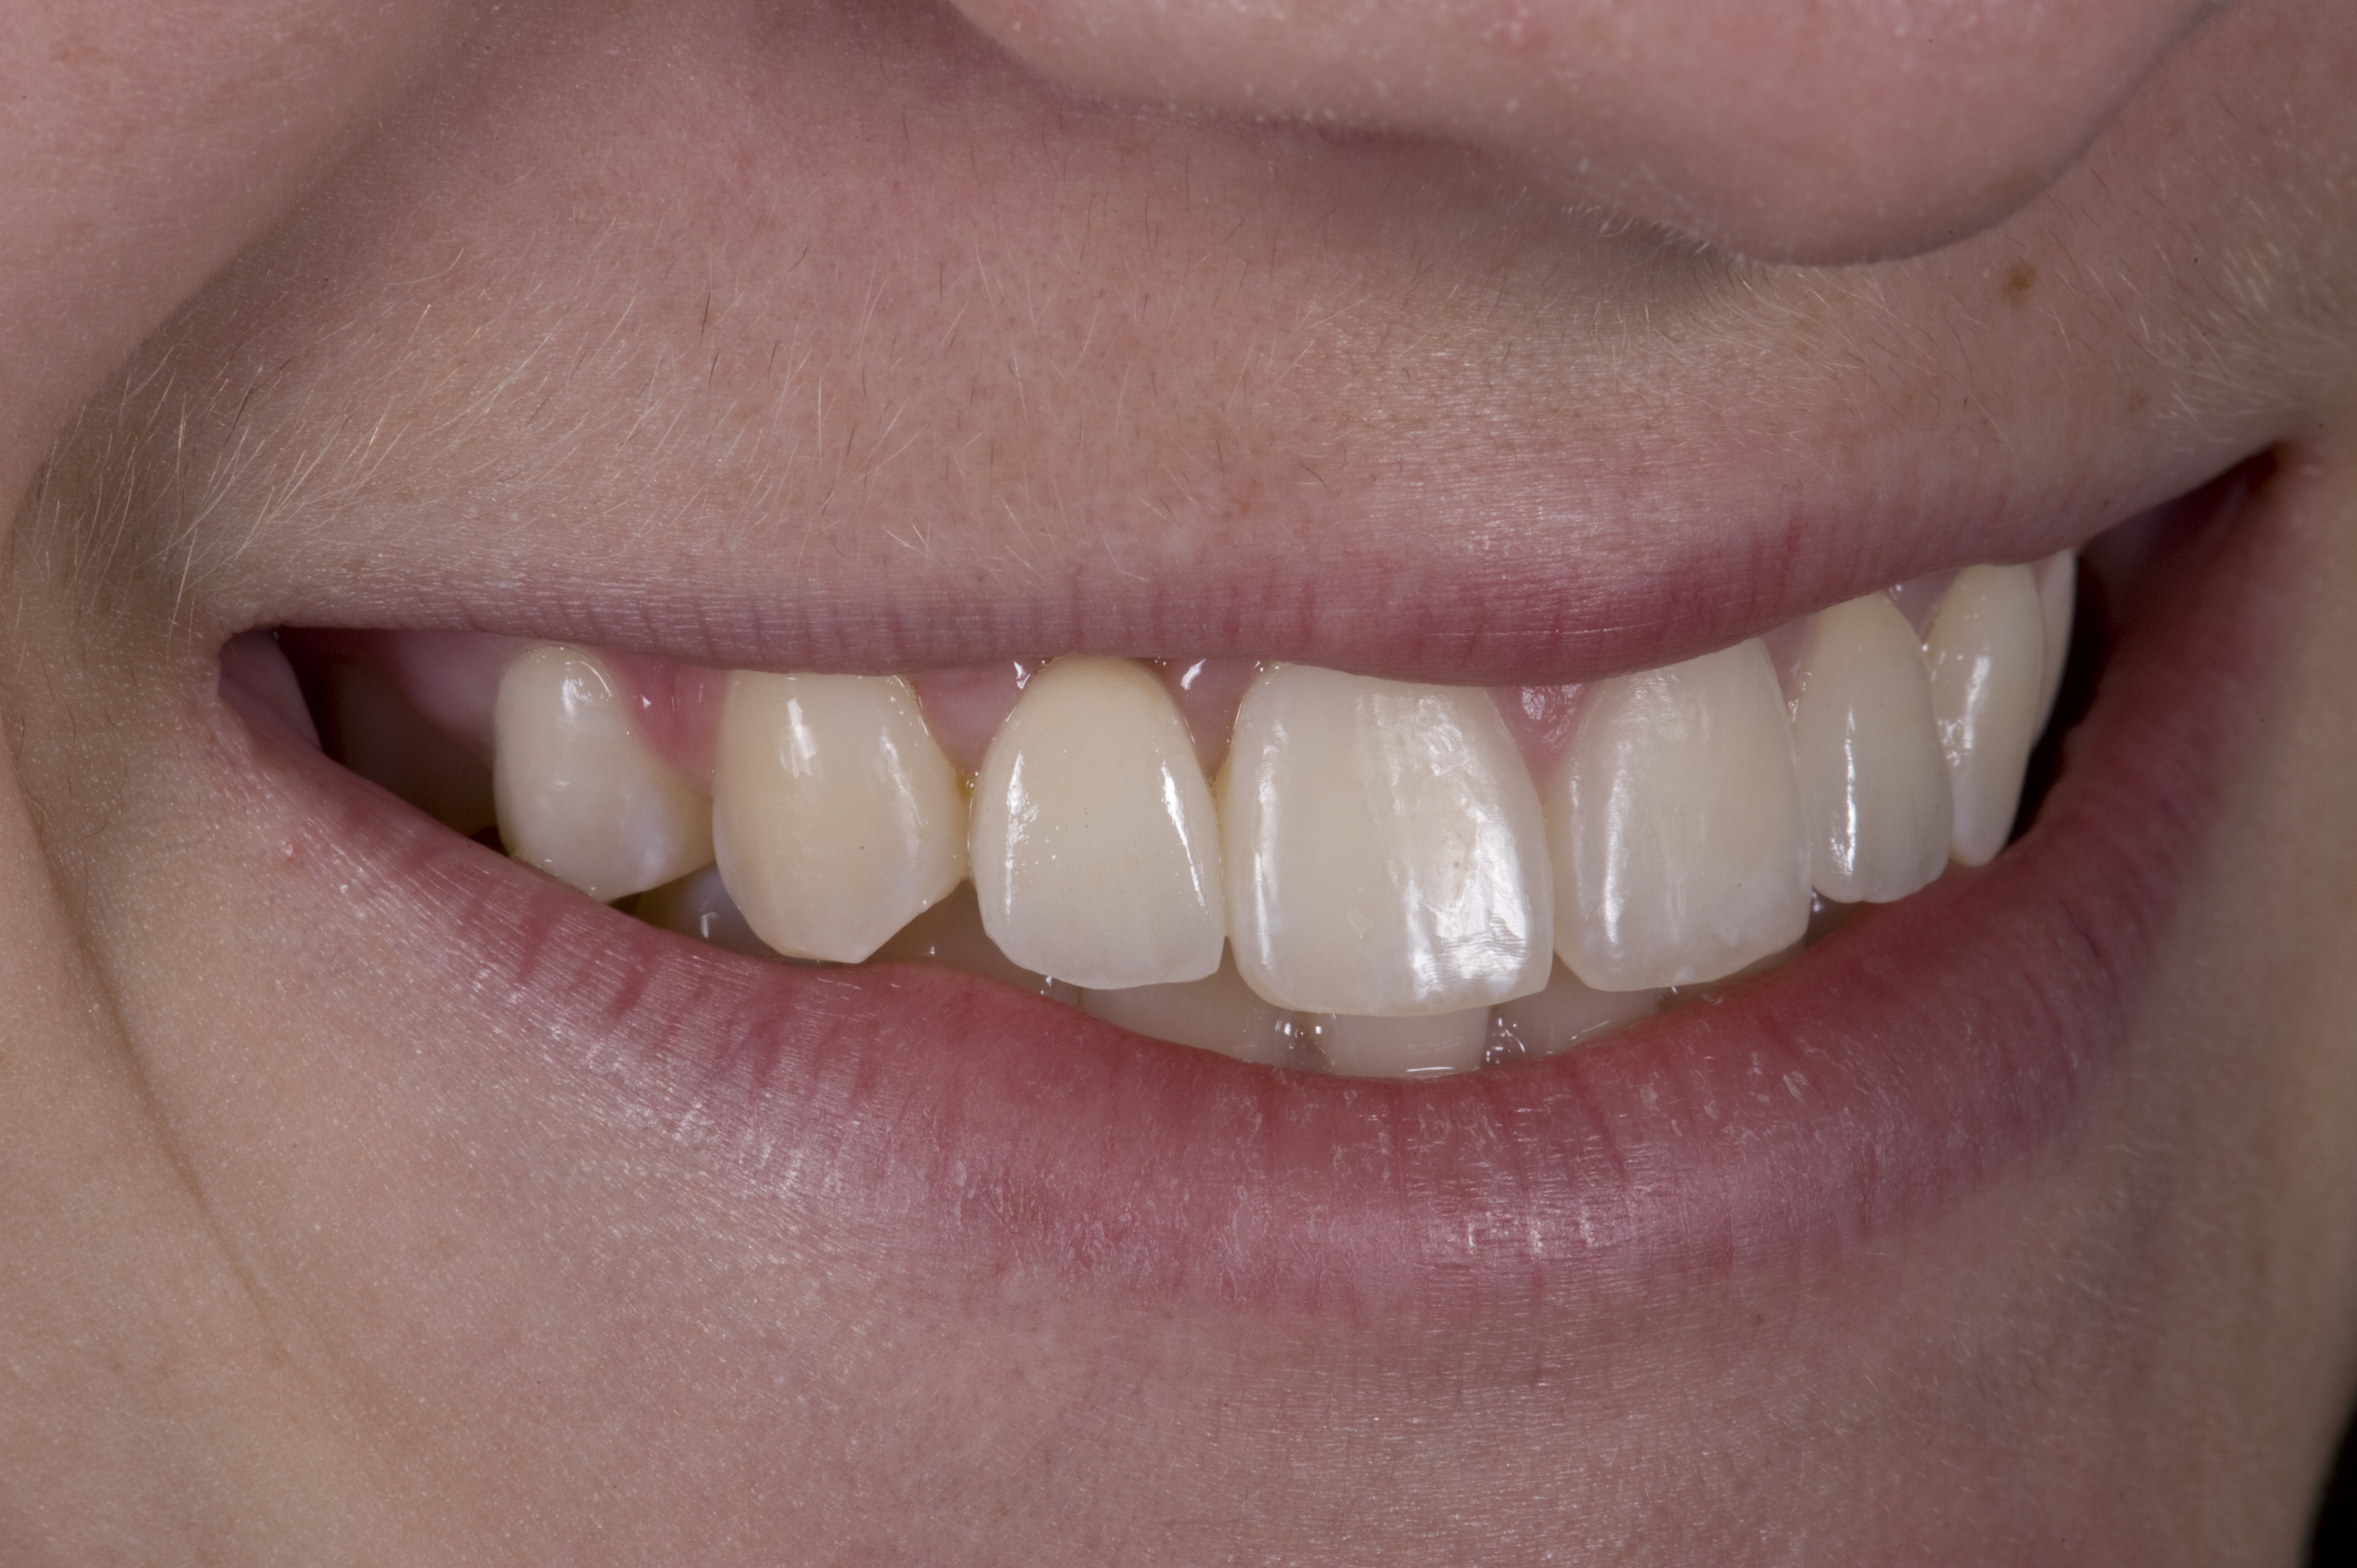

(12.) 15-year-old girl after orthodontic therapy idealized maxillary lateral incisor spaces.

Figure 12

Case Presentation 2: Patient Does Not Want to Have an Implant Placed

Some patients do not want an implant due to the need for surgical intervention, and others may not have enough space for implant placement. A 15-year-old patient presented to the office after completion of orthodontic treatment to idealize the spacing of her teeth and improve her occlusal relationship (Figure 12 through Figure 14). Because both of her maxillary lateral incisors were missing, the patient was wearing a retainer with lateral incisor pontics. She had a busy school schedule, but expressed her desire for a fixed restorative option. All of her options were discussed, and the patient was informed that if she wanted an implant, she would have to wait for at least 3 to 4 years for completion of growth. The patient was not sure if or when she wanted to have an implant placed in the future, especially considering her busy schedule and desire to attend college after high school. Considering her age and the need to be conservative, a single-wing zirconia Maryland Bridge was chosen as the ideal prosthetic replacement option. Because bonding a non-etchable and smooth surface such as zirconia requires chemical adhesion, it was decided to use a modified technique to make the bridge more retentive. One of the ways to improve adhesion of a zirconia bridge is to use an etchable feldspathic ceramic layer on the internal surface of the zirconia retainer.56-58 Unfortunately, it can be difficult to determine the thickness of the ceramic and ensure accurate seating of the restoration.